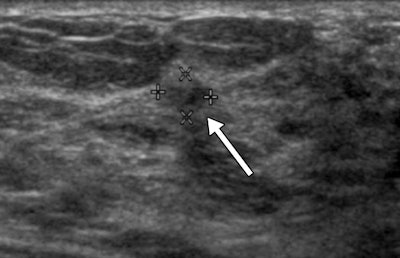

Out of 2,662 trial participants recruited between 2004 and 2006, 519 (19.5%) had 745 BI-RADS 3 lesions on ultrasound, representing 25% of all ultrasound-detected lesions in the study, according to the authors. Of these lesions, 124 (16.6%) were biopsied, and six of these biopsied lesions were malignant (representing 0.8% of BI-RADS 3 lesions). The average size of the detected cancers among the BI-RADS 3 lesions was 10 mm.

During follow-up imaging at six months, suspicious changes were observed in only one of the 745 lesions characterized as BI-RADS 3. At 12-month follow-up, suspicious changes were observed in a second BI-RADS 3 lesion, revealing an invasive breast cancer that had not yet spread beyond the breast.